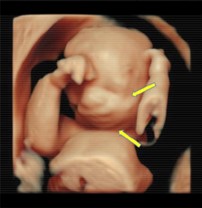

Mandibular hypoplasia

Prenatal 3D\4D ultrasound showing underdeveloped mandible

Radiographical features source 2